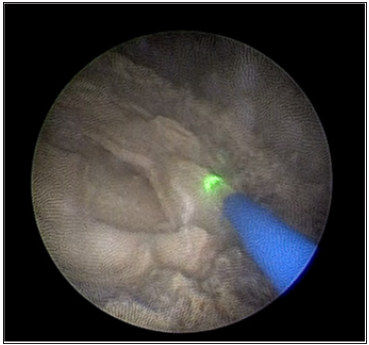

Figure 4:The fragmentation was performed using dusting mode with a 265μm HOLMIUM Laser fiber.

Under general anesthesia, we proceeded to a first progressive dilation of the orifice of the mitrofanoff, which was punctiform, with a hegar dilator until 16FR, then an introduction of a 9.5CH semirigid ureteroscope under visual control, neo-bladder exploration has shown no suspect lesion of the mucosa, the use of a 265μm HOLMIUM Laser fiber down ureteroscope permitted fragmentation of the stone using dusting mode (Figure 4) then fragmentation which were then removed with the zero tip basket. The procedure took 95 minutes and rendered the patient completely stone free (Figure 5). She was discharged the next day.